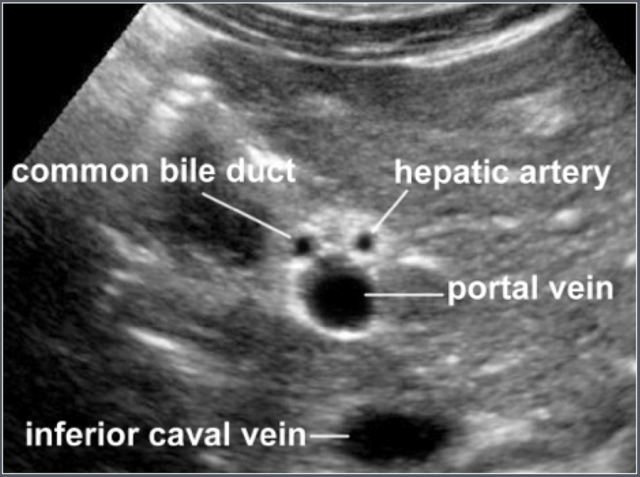

Common Bile Duct

Adapted from reference 8 Adapted from reference 8

Materials and method

One hundred and seventy-three consecutive children, referred for abdominal ultrasonography not related to hepato-biliary pathology, were included in this study (100 boys and 73 girls), age range 1 day - 13 years (median age 5.0 years).

The diameter of the common bile duct was ≤ 3.3 mm in all patients.

Transverse ultrasonographic image of common bile duct and surrounding anatomy

Portal vein

Adapted from reference 9 Adapted from reference 9

One hundred and fifty children aged 0-16 years, without clinical evidence of liver or intestinal disease, which were referred for abdominal ultrasound were included in the study.

Measurement of portal vein diameter Measurement of portal vein diameter

The portal vein is visualized in the longitudinal axis from the splenomesenteric junction to the liver hilum.

The greatest anteroposterior diameter is measured at the site where the hepatic artery crosses the portal vein.